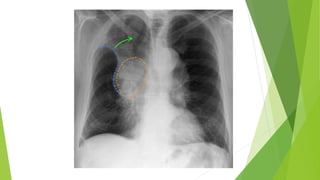

 Right upper lobe (RUL) collapse

#Elevation of the right hilum and the minor fissure

Lobar collapse  Rightupper lobe (RUL) collapse #Elevation of the right hilum and the minor fissure